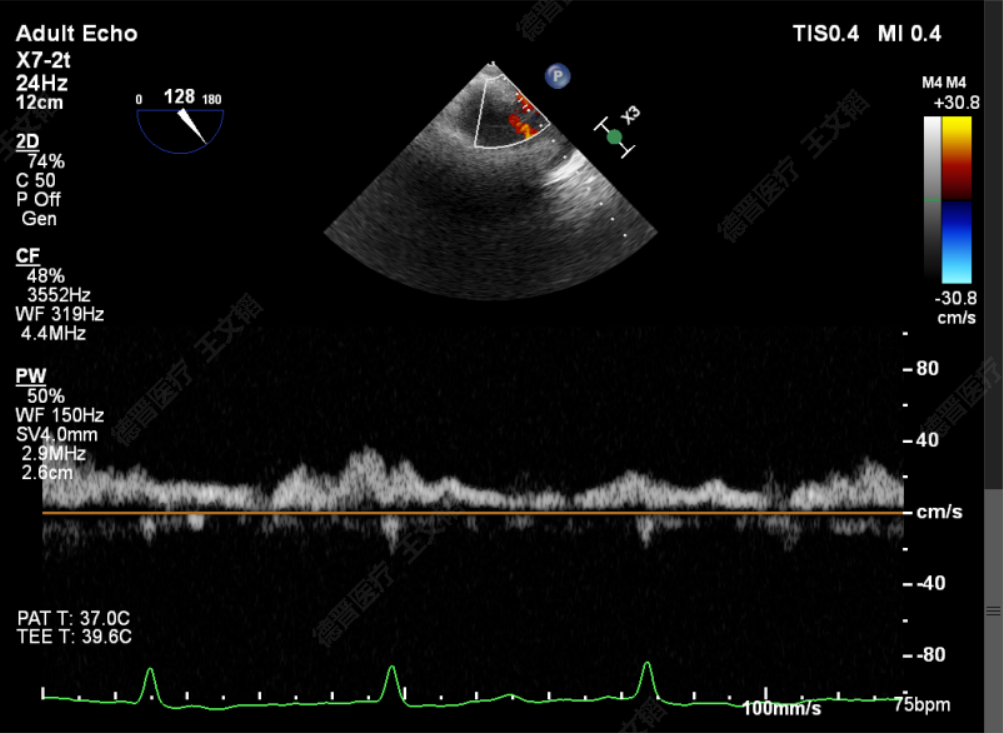

术中

TTE上彩评估无明显反流

L侧残余微量功能性反流

TMPG:1mmHg

肺静脉逆流消失